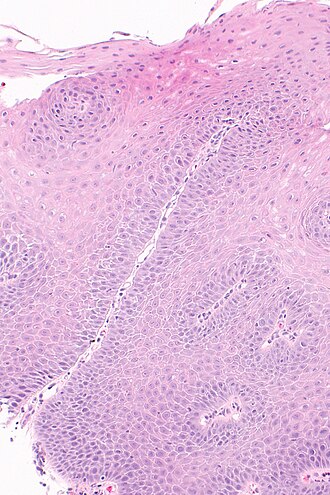

Template:Px Micrograph showing histology compatible with gastroesophageal reflux disease. H&E stain. | |

| LM | basal cell hyperplasia (> 3 cells thick or >15% of epithelial thickness), papillae elongated (papillae reach into the top 1/3 of the epithelial layer), inflammation, esp. eosinophils, lymphocytes with convoluted nuclei ("squiggle cells"), +/-intraepithelial edema, +/-apoptotic cells, +/-glycogenation |

| LM DDx | intestinal metaplasia (Barrett's esophagus), eosinophilic esophagitis, acute esophagitis |

Microscopic

Features:

- Basal cell hyperplasia;[5] > 3 cells thick or >15% of epithelial thickness.

- Papillae elongated; papillae reach into the top 1/3 of the epithelial layer.[6]

- Inflammation, esp. eosinophils, lymphocytes with convoluted nuclei ("squiggle cells").

- +/-Intraepithelial edema.

- +/-Apoptotic cells.[7]

- +/-Glycogen - cytoplasm cleared (white).[8]

- Gastroesophageal reflux disease -- intermed mag.jpg

GERD - intermed. mag.